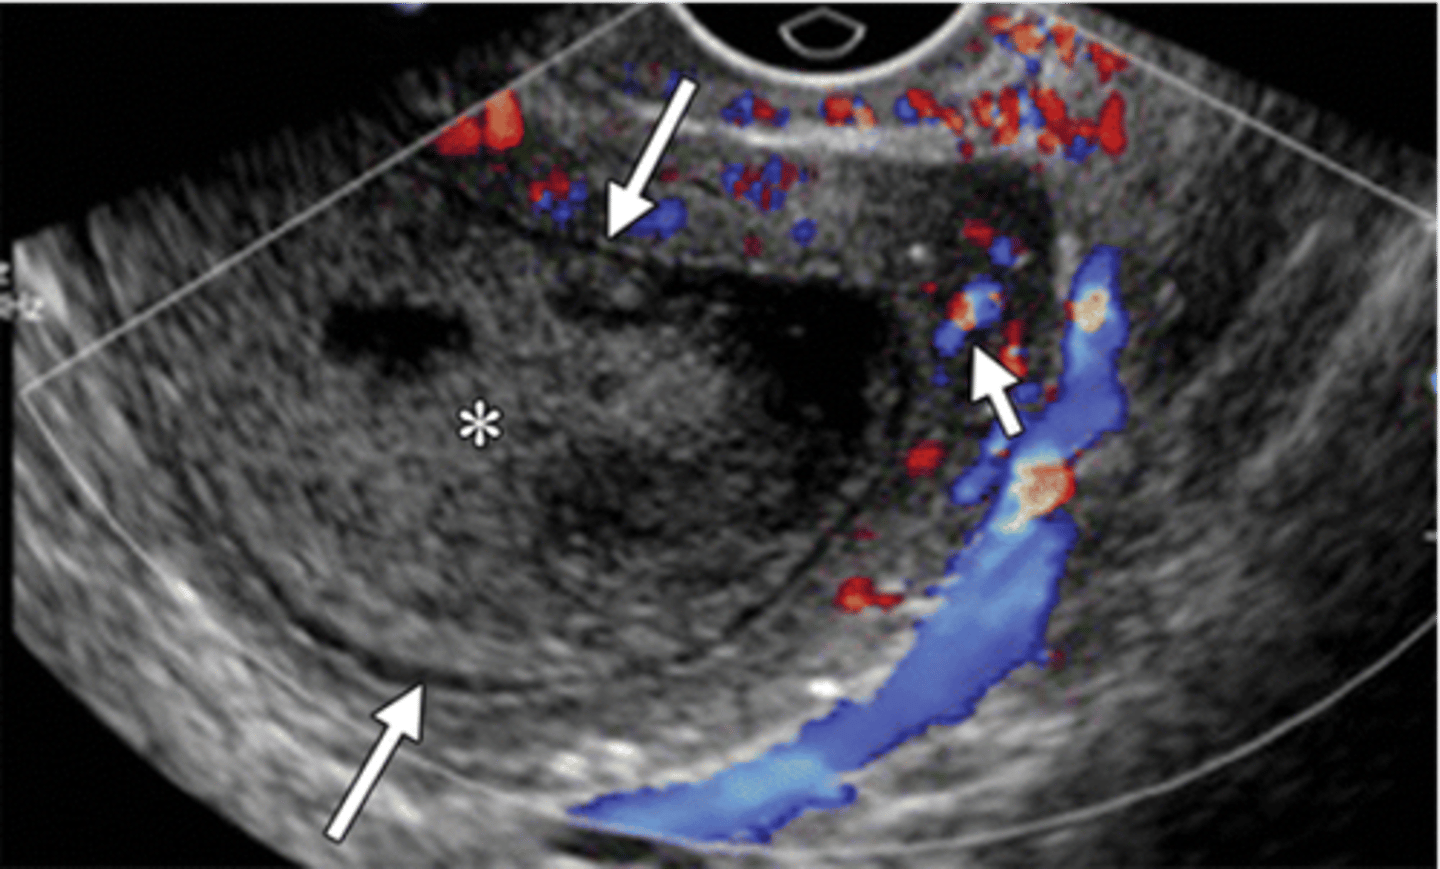

you do a transvaginal sono on your patient with suspected PID. what may you see?

Hyperemia

Dilated uterine cavity

Thickening of the tubes

Fluid in the uterus or tubes

Free-fluid in the pelvis

what does late PID look like?

dilated endometrial canal (long arrows), hyperemia of myometrium (short arrow), uterine wall thinning